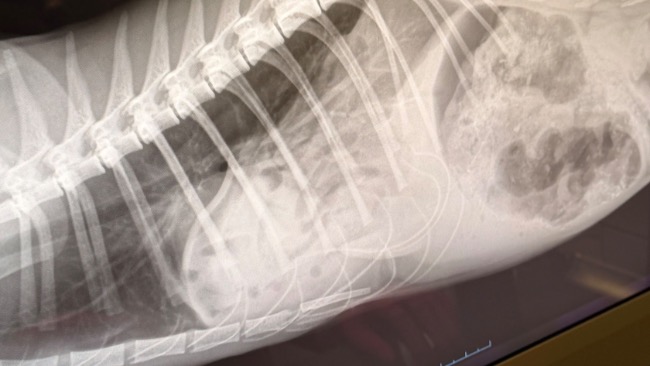

Obraz RTG przed operacją:

Ginger trafiła do nas skrajnie wychudzona, osłabiona, w stanie bezpośredniego zagrożenia życia. Badanie RTG nie pozostawiło wątpliwości. Przepuklina przeponowa wymagała natychmiastowej interwencji chirurgicznej. Nie było czasu na zwłokę. Każda godzina mogła odebrać jej szansę.